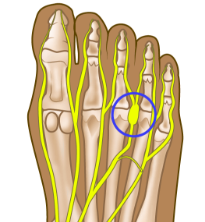

Neuroma

A painful condition affecting the nerves between the toes. Treatment includes orthotics, injections, and sometimes surgery.